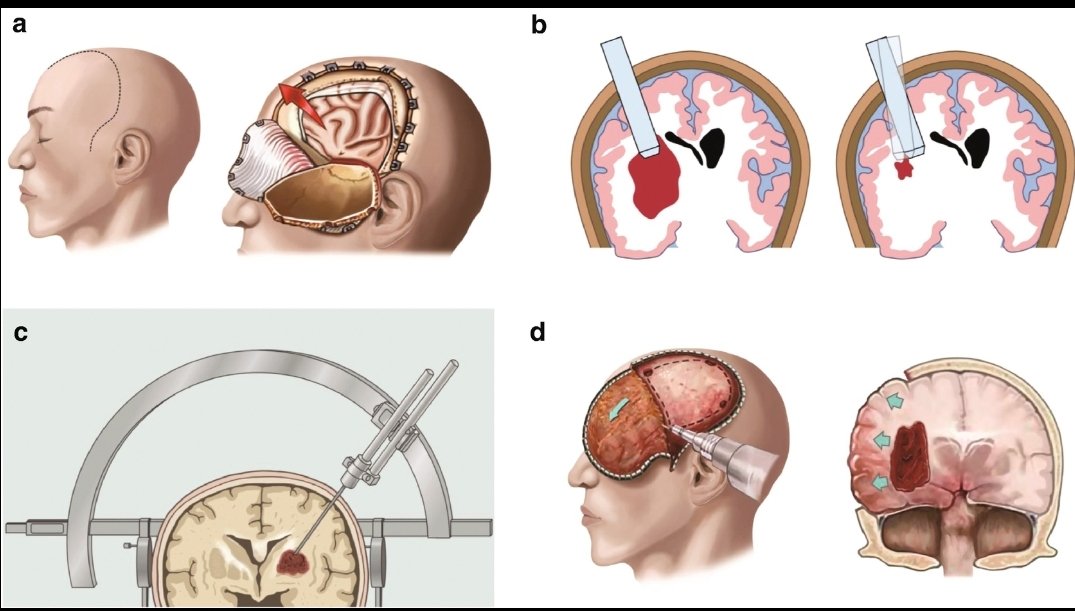

#السكته_الدماغيه_النزفيه

🧠علاجها

💥السيطرة ع #ضغط_الدم

💥السيطرة على سبب النزيف ومضاعفاته ( ان وجدت )

اما بالتدخل الجراحي او العلاجات الدوائيه او كلاهما

💥إيقاف علاجات السيوله ان وجدت

💥علاج المضاعفات ان وجدت ك #التشنجات او #الصداع او تضيق الشرايين العكسي

💥علاج السبب الاساسي

💥هنالك حالات يزداد فيها الضغط داخل الجمجمه

💥بسبب

🧠تجمع السوائل

🧠غزارة النزيف

🧠 كبر حجم التجمع الدموي

💥ولان العظم لايتمدد

فقدرته محدده لاستيعاب الحجم الزائد

فنضطر بشروط معينه

🧠اعطاء علاجات ومدرات

🧠وضع أنبوب تصريف

🧠ازالةجزء من الجمجمه

💥هنالك حالات يزداد فيها الضغط داخل الجمجمه